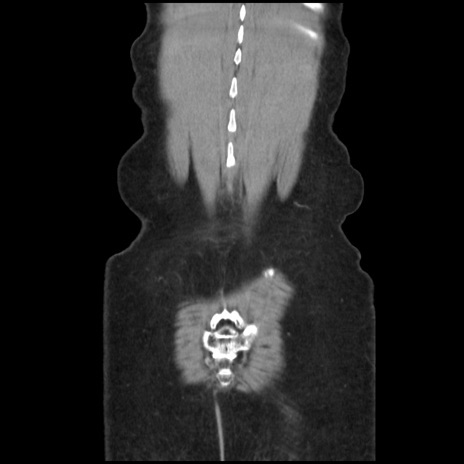

矢状断像